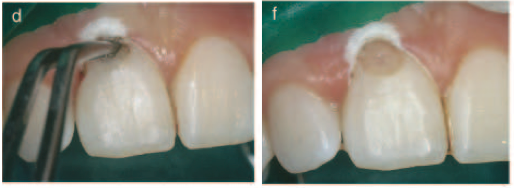

Case 3– #19 Class II ECIR with LuxaCore buildup

33 y/o female presented complaining of an intermittent dull ache and hot/cold sensitivity. Radiographic and CBCT exams revealed Class II ECIR overlying the M pulp horn and extending to the ML osseous crest (A, B, C). Clinical exam revealed secondary caries had infiltrated the lesion, resulting in an irreversible pulpitis. Endodontic treatment was completed on the first visit and the tooth was temporized with cotton and cavit (D). The patient returned a week later and the ECIR defect was prepped out. I soaked the area with 90% trichloracetic acid to ensure the removal of all resorptive tissue. An MOBL LuxaCore (dual cure composite) buildup was placed (E, F) and the patient was referred back to her general dentist for the crown. Recall not yet available.